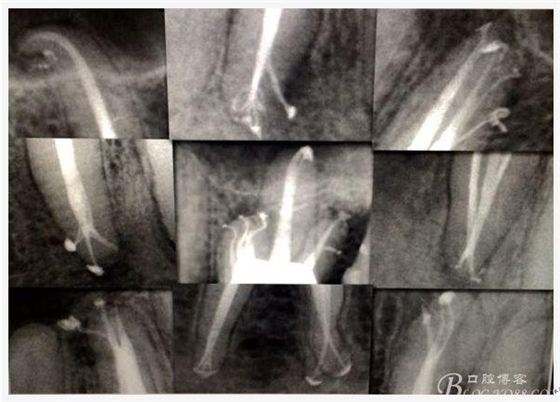

C、牙根的折裂與隱裂 包括橫折,縱折,或者斜折,外傷類的不用討論,主要是某些特殊原因比如牙齒本身結(jié)構(gòu)先天性缺陷再配合后天因素如牙合創(chuàng)傷、咬合平衡發(fā)生改變導致應力集中,或者某次瞬間的咬合暴力等一種或者多種因素作用的結(jié)果,具體什么原因這個要從多方面因素權(quán)衡來判斷,比如牙齒的松動度,詢問病史,找不出其它原因時的重點懷疑,牙齒本事是否處于合應力集中的區(qū)域,是否有不良修復設計等等,具體可以通過臨床“理化檢查(冷熱,叩診等)”再結(jié)合數(shù)值化小牙片,牙髓活力測定,以及CBCT等來綜合判斷,重點懷疑牙為上頜的4/5的頰或者腭根,尤其是4或者5的遠中已是游離缺失或者單端橋等,6的腭根以及下頜的4/5/6都是重點懷疑對象,而最難診斷的是牙根的隱裂,即使使用CBCT有時候也沒辦法確診;

D、牙根的內(nèi)外吸收 這個目前具體機制也不是非常明確,只要能想到這個層面,通過X片檢查不難發(fā)現(xiàn),尤其到了有臨床癥狀的時候;